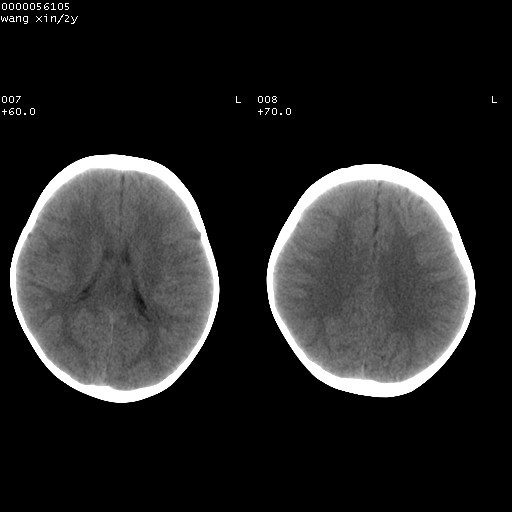

标题: PED1611:F,2Y。右侧额部小包块,光整,质硬,边界清楚,无 [打印本页]

标题: PED1611:F,2Y。右侧额部小包块,光整,质硬,边界清楚,无

右额骨内板压迫性变薄,呈椭圆形膨胀性骨吸收和低密度区,其间可见小斑片状致密影,-支持表皮样囊肿

考虑右侧额骨表皮样囊肿.双侧上颌窦\\筛窦炎.